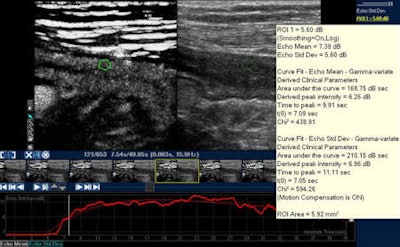

Contrast-enhanced ultrasound of the bowel after sulphur hexafluoride-filled microbubble injection. Analysis of bowel wall perfusion with a quantitative software (intensity curve versus time). Image courtesy of Dr. Carla Serra.CEUS is already showing potential in chronic inflammatory bowel disease evaluation, especially for the assessment of activity in Crohn's disease (CD), she noted. The technique involves intravenous administration of an ultrasound contrast agent with real-time examination, and can provide an accurate depiction of the bowel wall microvascularization and the perienteric tissues. The introduction of quantification techniques enables objective quantitative measurement of the enhancement.

The software makes it feasible to immediately export data in Excel and collect it for future patient visits or comparison with other patients. In a quantification method for CD, it is possible to view the region-of-interest and, during the injection time, the arrival and amount of contrast, as well as the typical wash-in and wash-out curves. Several studies have shown that this technique has both high specificity and sensitivity in evaluating treatment results, but translating these advances into clinical practice remains challenging because one examination is still very different to another.